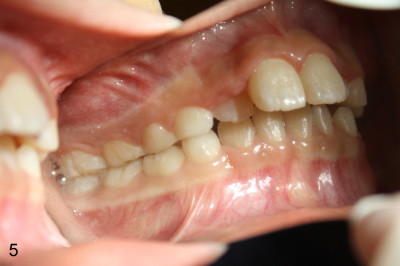

Eight-year-four-month-old boy shows early signs of Class II Division I malocclusion (Fig.2-5).  Panoramic X-ray was taken when he was 5 years 10 months old (Fig.1).

Is there any indication for phase I ortho (interceptive treatment)?  In my opinion, early orthodontics will improve appearance.  Additional Class II retraction may change canine and molar Class II occlusion into Class I so that the mandible may develop normally before permanent dentition.  If the early treatment is not done until permanent dentition as parents hope, it is most likely that orthodontics will be conducted with extraction at least two upper bicuspids.  The father has typical Class II Division I malocclusion.  What do you think?  Thanks.

2nd reply Also Xin in your case of the 8 y.o. boy, I could make the argument that the lingually positioned #7 and #10 may ultimately restrict the lower jaw from growing normally anteriorly.  Their position may very well indeed be in the way.  Check out occlusion from your pictures.  I can explain better in person perhaps.